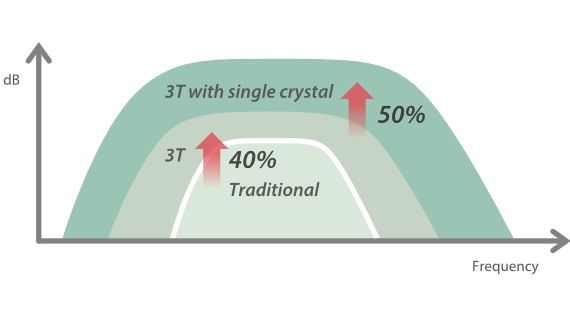

–°–Њ–≤–Љ–µ—Б—В–љ–Њ —Б —Б–Њ–≤—А–µ–Љ–µ–љ–љ—Л–Љ–Є —Г–ї—М—В—А–∞–Ј–≤—Г–Ї–Њ–≤—Л–Љ–Є —В–µ—Е–љ–Њ–ї–Њ–≥–Є—П–Љ–Є –љ–Њ–≤–Њ–µ —А–µ—И–µ–љ–Є–µ –Њ—В Mindray –њ—А–µ–Њ–±—А–∞–Ј—Г–µ—В –∞–Ї—В—Г–∞–ї—М–љ—Л–µ –Ј–∞–і–∞—З–Є –Ї–ї–Є–µ–љ—В–Њ–≤ –≤ –Ї–ї–Є–љ–Є—З–µ—Б–Ї–Є–µ –њ–Њ—В—А–µ–±–љ–Њ—Б—В–Є.

–Ю—Б–љ–Њ–≤—Л–≤–∞—П—Б—М –љ–∞ –≥–ї—Г–±–Њ–Ї–Њ–Љ –њ–Њ–љ–Є–Љ–∞–љ–Є–Є –њ–Њ—В—А–µ–±–љ–Њ—Б—В–µ–є –Ї–ї–Є–µ–љ—В–Њ–≤, –Ї–Њ–Љ–њ–∞–љ–Є—П Mindray —А–∞–Ј—А–∞–±–Њ—В–∞–ї–∞ —Б–Є—Б—В–µ–Љ—Г DC-70 Exp —Б X-Insight, —З—В–Њ–±—Л –Њ–±–µ—Б–њ–µ—З–Є—В—М eXpress Clarity, eXceptional Intelligence, eXceeding Experience.